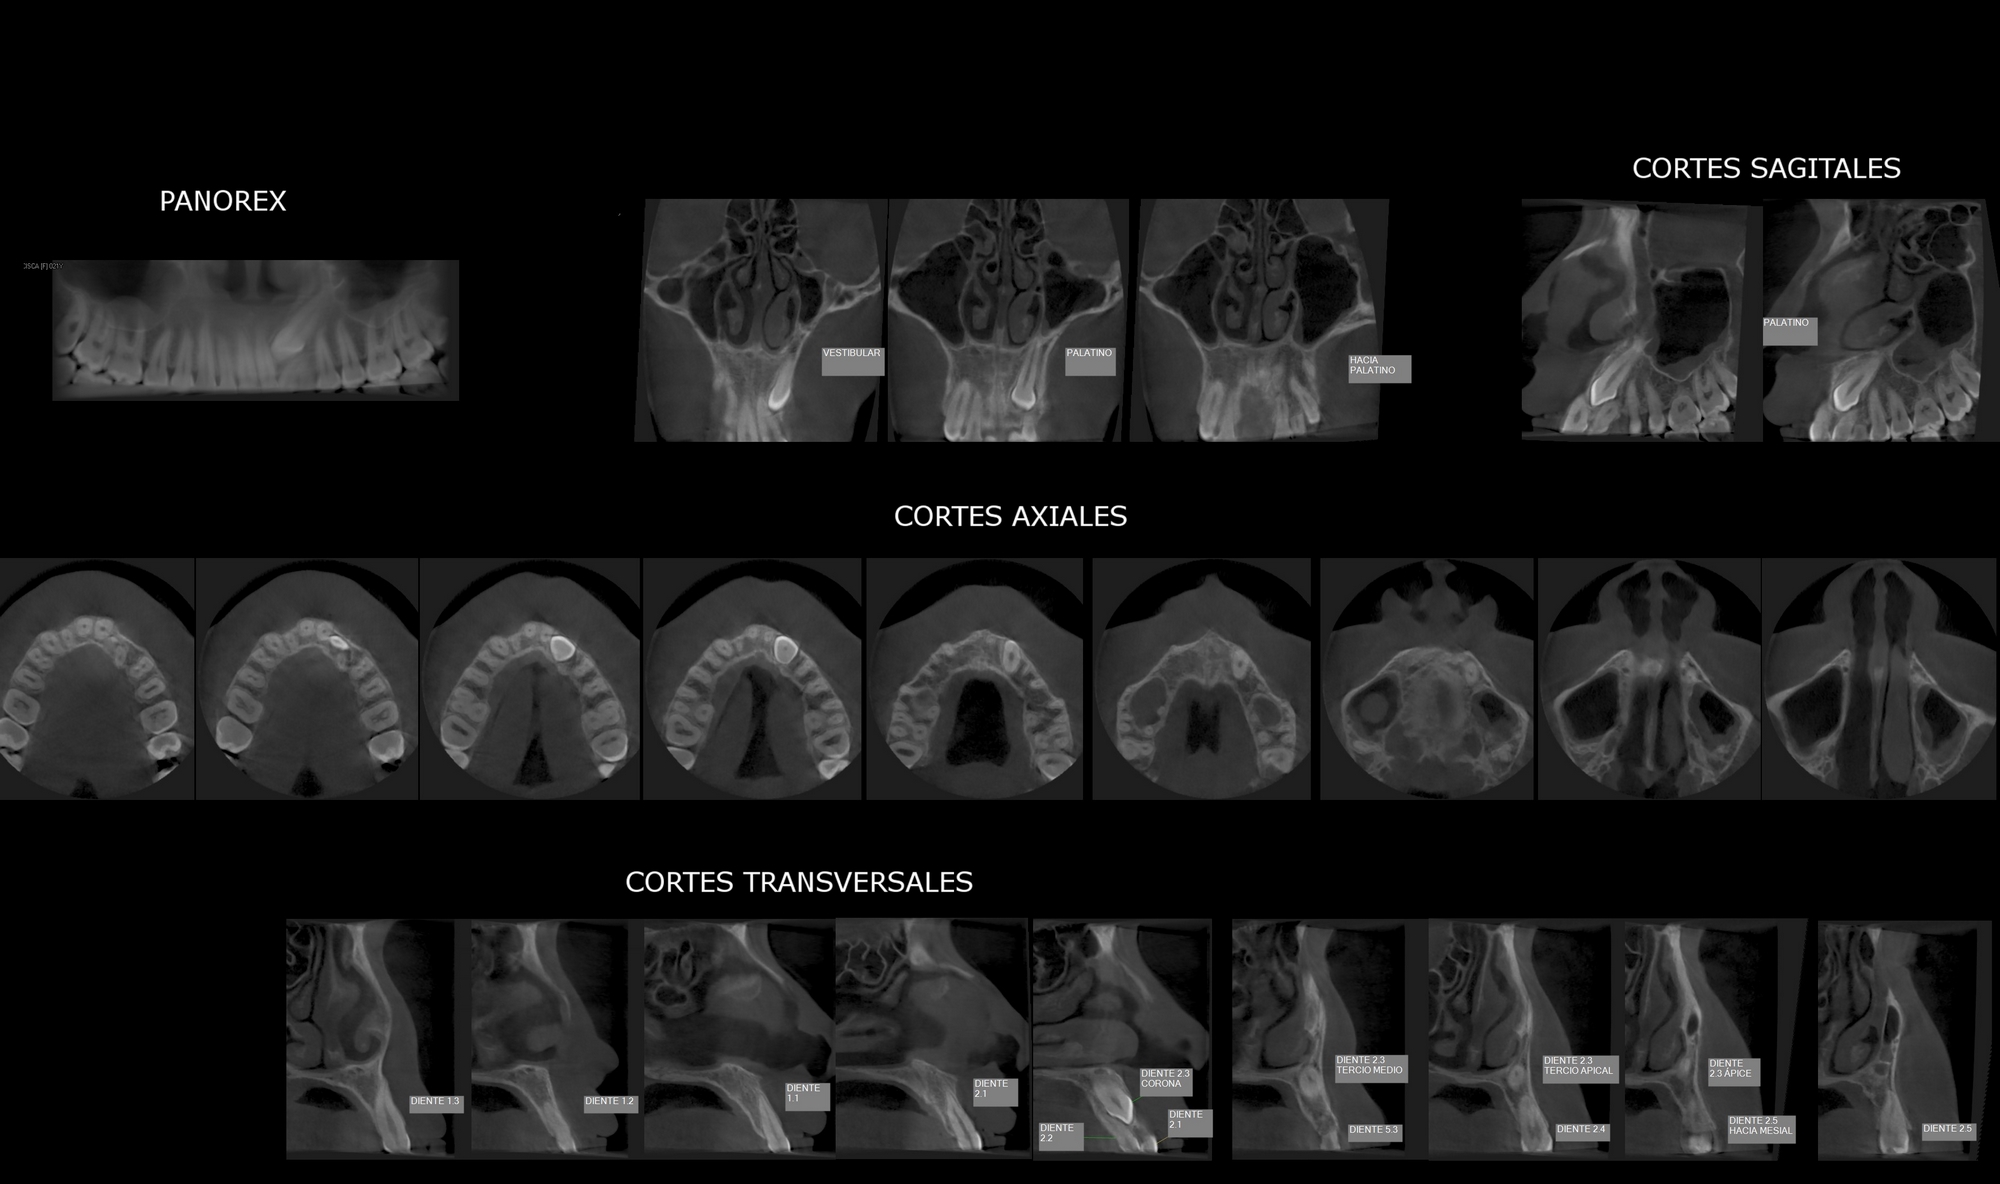

Tomografía 3D

Rx Panorámica 3D

- En parte, cortes en 2D libremente inclinables

- Cortes en 3D libremente seleccionables

- PAN, TSA, LSA, axial, sagital, coronal, modelo 3D